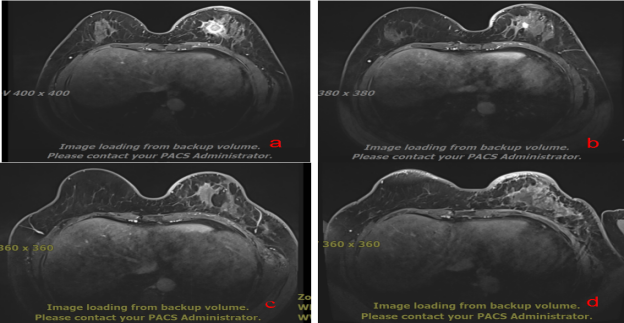

45岁,左乳恶性肿瘤 T4bN3M0 IIIc期, 图a碳离子治疗前,图b碳离子治疗后,图C碳离子治疗后3个月,图d 碳离子治疗后6个月,完全缓解,疗效达CR。